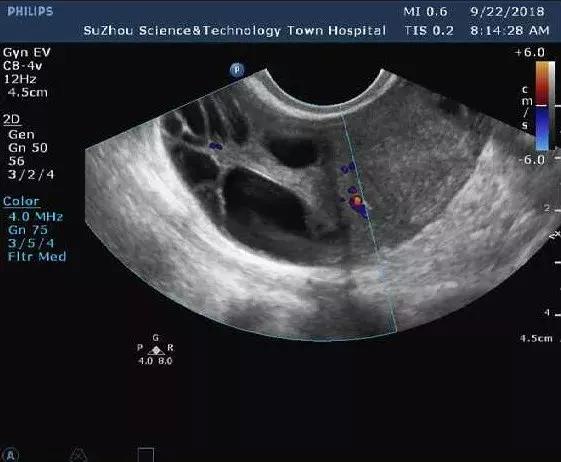

而“卵巢多囊样改变”则是指在卵泡早期超声检查一侧或双侧卵巢直径2~9mm的卵泡超过12个或卵巢体积超过10ml。据临床调查研究发现,在正常女性当中也有有20%-30%同时伴有卵巢多囊样改变,但不代表她们就是有多囊卵巢综合征。

(3)卵巢多囊改变